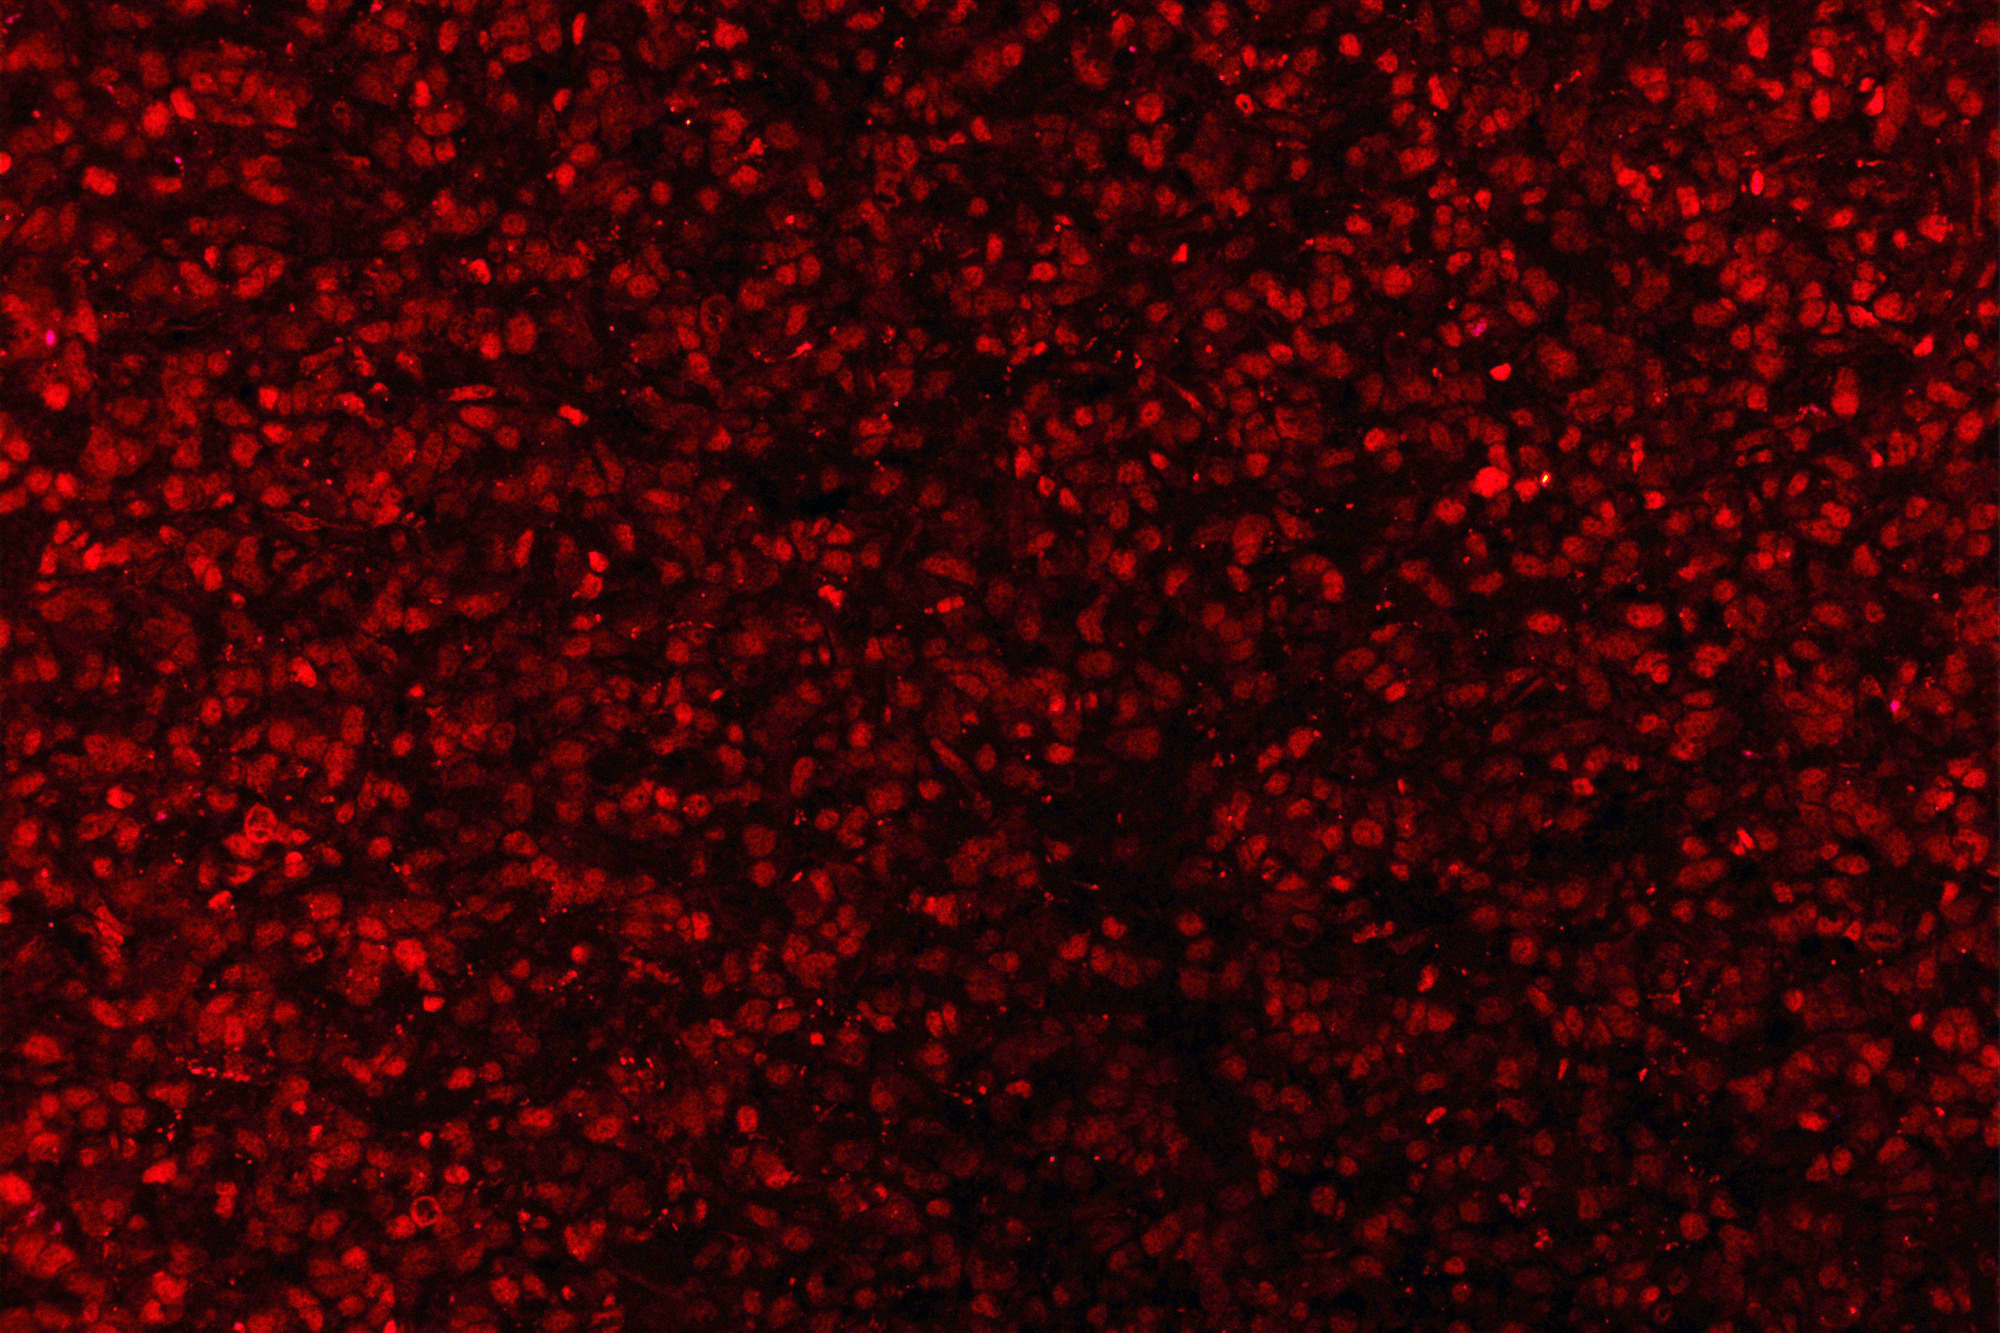

IF analysis using anti- ZEB1 antibody (M00548-2). detected in paraffin-embedded section of human Glioma tissues. The tissue section were stained using the Dylight550-conjugated Anti- mouse IgG Secondary Antibody (red)(Catalog # BA1133).